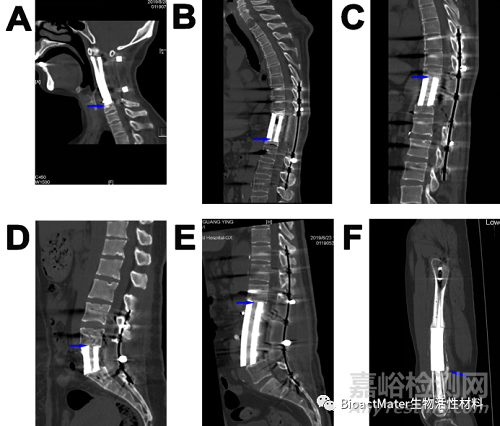

圖S3. 頸椎(A)、胸椎(B、C)、腰椎(D、E)和股骨(F)缺損患者的“種植體-骨”界面融合是由于骨通過(guò)多孔種植體生長(zhǎng)(A-E中的藍(lán)色箭頭所示)或外表面的礦化骨痂橋接(F中的藍(lán)色箭頭所示)。